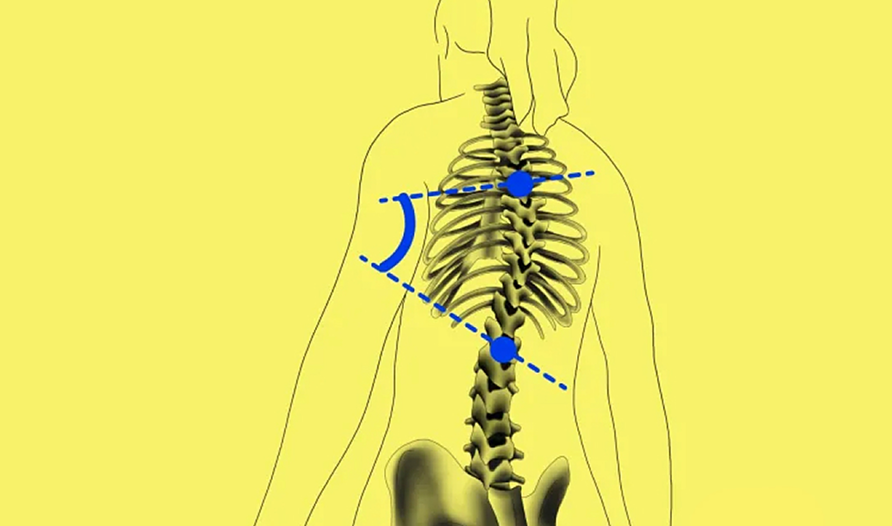

BoneMetrics automatically performs standard measurements for the feet, legs, pelvis/hips, and spine.

Through accurate point placement and easily understandable displays, the introduction of the software allows you to direct your attention to more critical tasks.

By introducing AI-supported standardization, variability can be reduced and reproducibility can be ensured.

Clinical studies prove that BoneMetrics matches the expertise of MSK radiologists, enabling your practice to provide the best possible service to patients.

BoneMetrics instinctive reports seamlessly integrate with your X-ray and EOS acquisitions, streamlining the interpretation procedure and elevating the satisfaction of your prescribers.